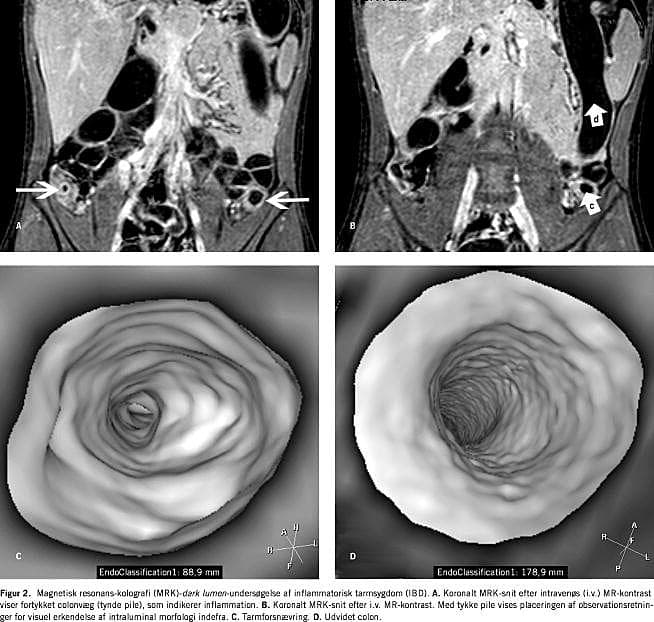

Udviklingen af kraftigere computere og MR-skannere har gjort det klinisk muligt at undersøge hele colon ved hjælp af MRK. Primære undersøgelser tyder på, at MRK er egnet til påvisning af kolorektale tumorer (polypper eller cancer) (Figur 1 ) og diagnostik af inflammatorisk tarmsygdom (IBD) (Figur 2 ).

MR anvendtes i stigende omfang til diagnostik af tyndtarmsforandringer ved Crohns sygdom [1, 13, 14]. I de senere år er MRK, som benytter planar rekonstruktionsdataanalyse, også blevet anvendt ved IBD i colon [10, 12-14, 36]. Ved IBD koncentreres interessen om de tre kriterier: tykkelsen af colonvæg [10, 14, 37], tarmforsnævring og øget optagelse af kontrast givet intravenøst [10, 14, 38, 39]. Intensitetsstigningen i inflammeret tarmvæg er mindst dobbelt så stor som i en rask tarmvæg, hvilket giver metoden en høj sensitivitet. Tarmforsnævring og colonvægtykkelsen korrelerer med de inflammatoriske ændringer. Desuden er det muligt at identificere inflammerede tarmområder i jejunum og den proksimale ileum, som det kan være problematisk at finde med den konventionelle koloskopi [14]. Intensitetsstigningen er dog afhængig af sygdomsaktiviteten på undersøgelsestidspunktet. Det er derfor ikke mærkeligt, at Schreyer et al [13] fandt, at der er lige så mange publikationer, som viser en god korrelation mellem MR og Crohns sygdom-aktivitetsindeks (CDAI), som publikationer, der viser ringe korrelation. Området er således langtfra færdigudforsket.

Der forligger ikke opgørelse r, der er fokuseret på anvendelsen af virtuel koloskopi ved IBD. Ved virtuel koloskopi finder man kun intraluminal morfologi med detaljer > 5 mm [13]. Derfor kan små colonoverfladedeformationer og erosioner ikke erkendes visuelt.